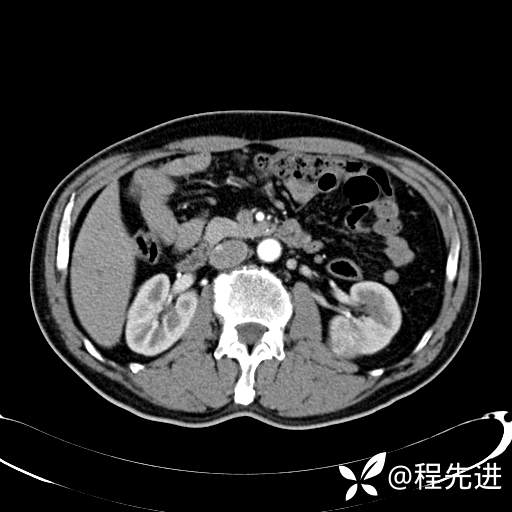

患者性别:男

患者年龄:65岁

简要病史:腰痛2月,体检发现左肾占位5天

排泄期:

肾透明细胞癌 (27)